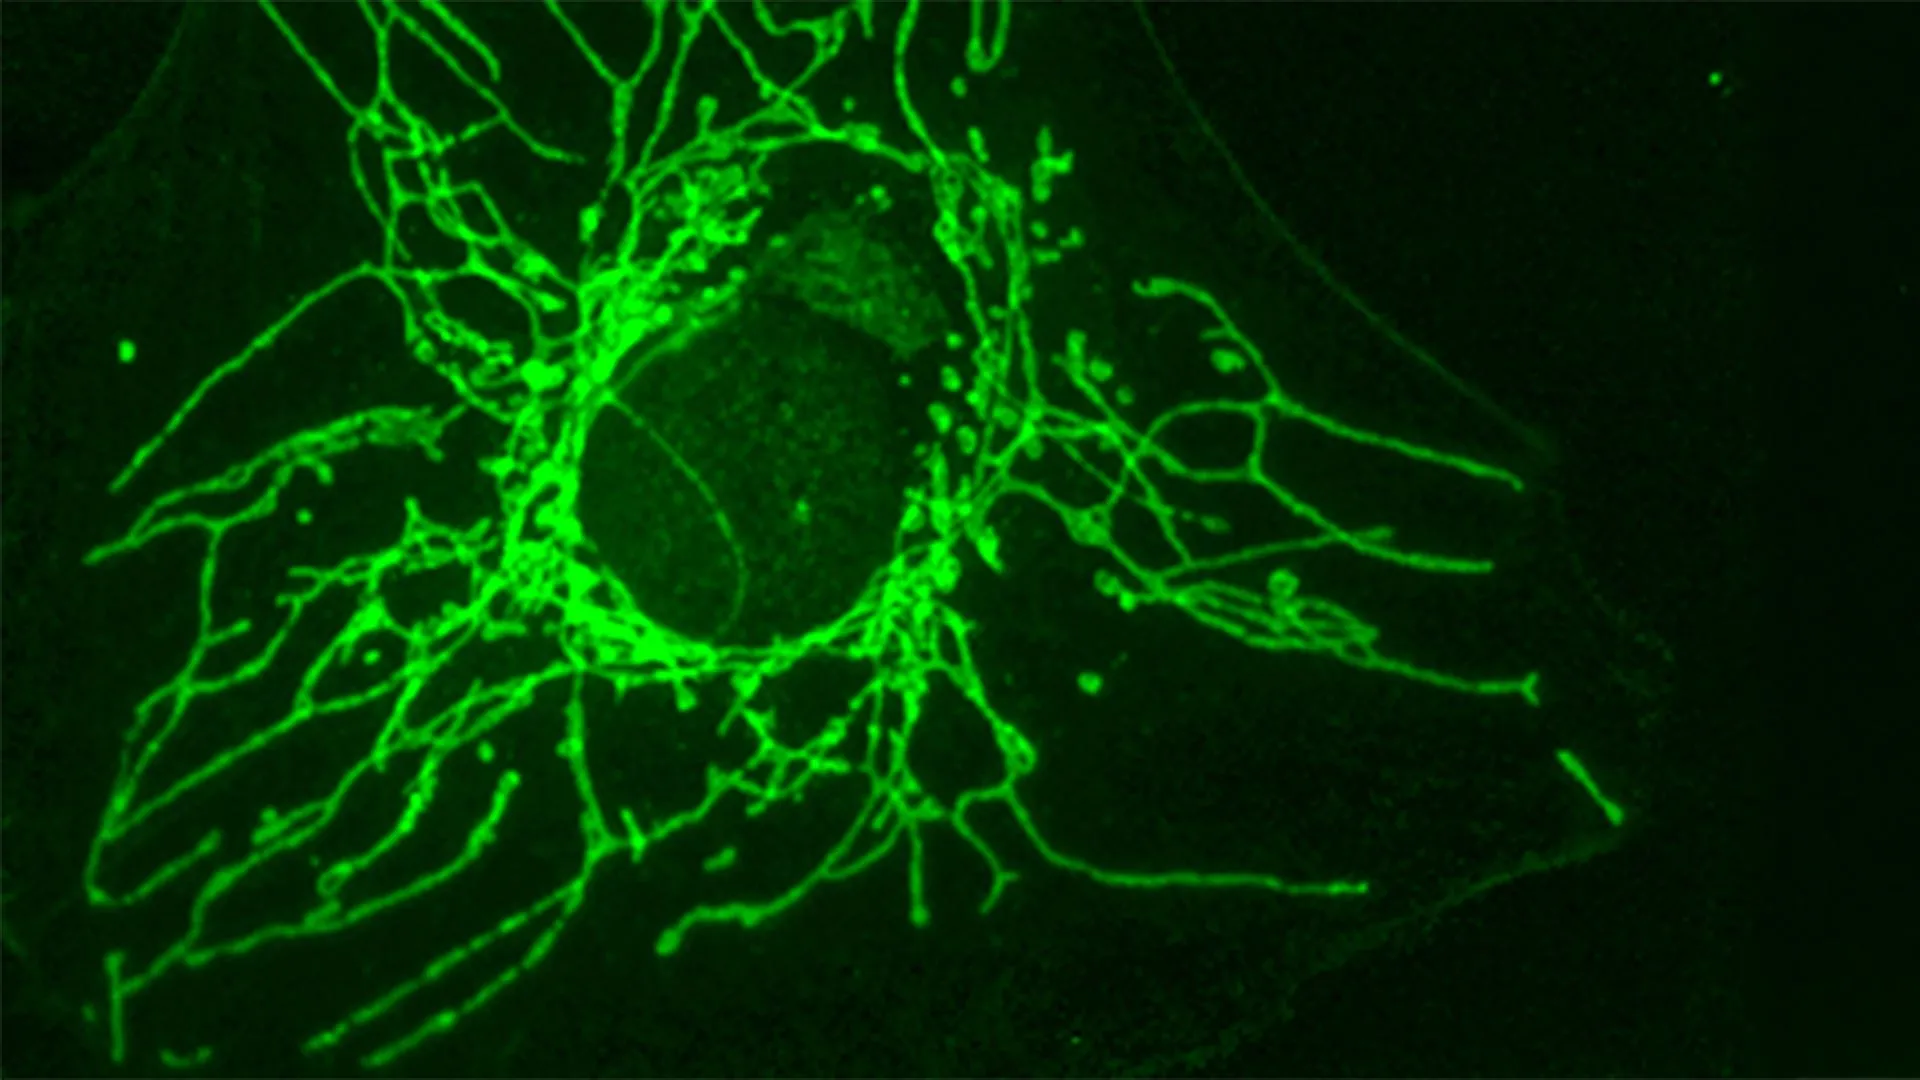

Collaborating with Professor Roland Lill and his esteemed team at the University of Marburg, the UNIGE researchers delved deeper into the intricate molecular mechanisms by which D-Cys exerts its cytotoxic effects on cancer cells. Their investigations pinpointed a critical target: an essential enzyme named NFS1, located within the mitochondria, the cellular powerhouses responsible for energy production.

"It blocks an essential enzyme called NFS1, located in the mitochondria — the cell’s ‘powerhouses’," Professor Lill stated in a joint statement released following the study’s publication. "This enzyme plays a key role in producing iron-sulfur clusters, small structures that are indispensable for many processes such as cellular respiration, DNA and RNA production, and maintaining genetic integrity."

Iron-sulfur clusters are vital cofactors for a multitude of cellular enzymes, playing critical roles in electron transport chains (essential for energy generation through cellular respiration), DNA replication and repair, and the synthesis of RNA. When NFS1 is inhibited by D-Cys, the production of these crucial clusters is severely hampered. This disruption triggers a cascade of detrimental effects within the cancer cell. Cellular respiration falters, leading to a significant reduction in energy supply. Simultaneously, DNA damage accumulates, and the cell cycle, the ordered series of events that leads to cell division, becomes arrested. These combined assaults effectively halt the cancer cell’s ability to grow, divide, and propagate, thereby controlling tumor progression. The elegance of this mechanism lies in its multi-pronged attack on fundamental cellular processes that are particularly critical for rapidly dividing cancer cells.